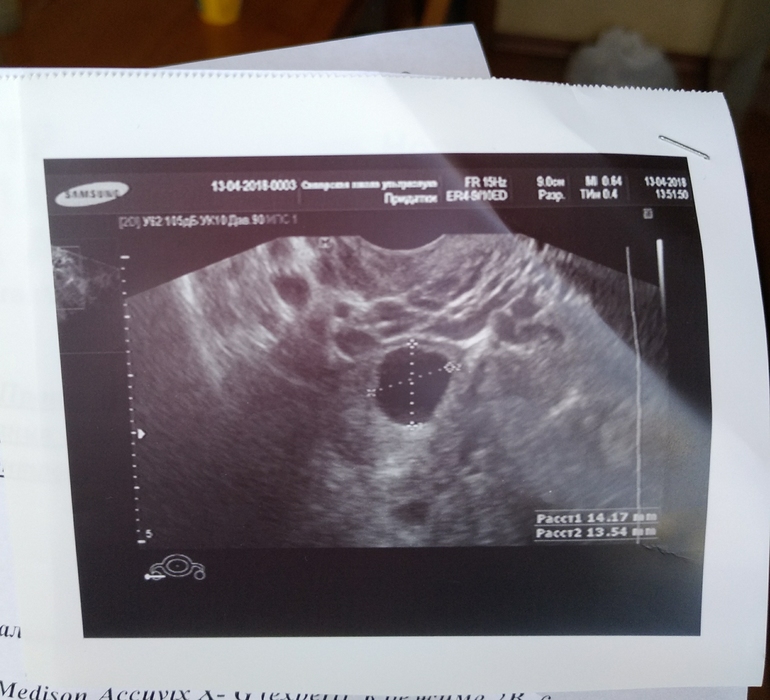

На 19дц рухнула БТ, на УЗИ врач ничего не поняла, сказала вроде фолликул, а при доплер методе кровоток уже как ЖТ,и это что-то размером 14х13. эндометрий ранней секреции, жидкость особо не смотрела, бегло сказала что её нет,(значит и О нет? или ее реально н е увидеть?)

На фото у вас фолликул. Жт серого цвета с вкраплениями в центре

Больше на жт похоже. Фолликул обычно прям совсем ровный по краям